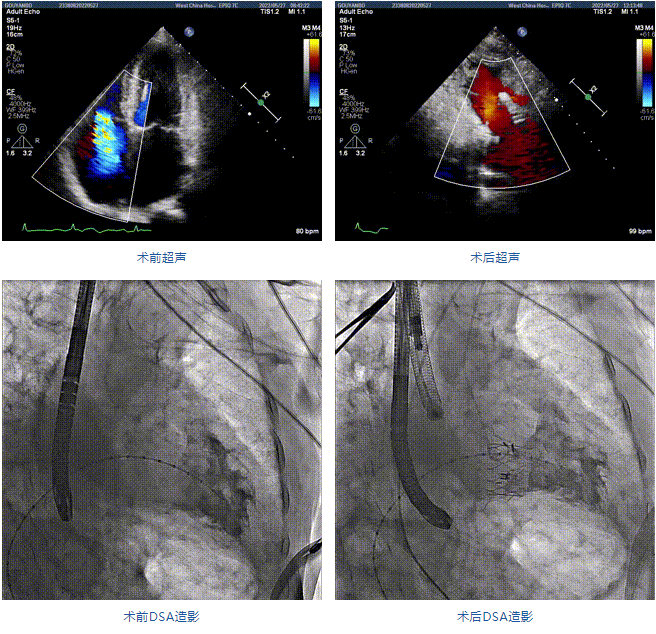

89歲男性。術(shù)前超聲報(bào)告顯示:雙房增大,左室壁肥厚,主、肺動(dòng)脈增寬,三尖瓣重度反流。

團(tuán)隊(duì)前期經(jīng)過多次討論,制定了周密的手術(shù)策略和預(yù)案。由于患者已是近九旬的超高齡老人,傳統(tǒng)外科開胸手術(shù)風(fēng)險(xiǎn)極高,純介入經(jīng)血管三尖瓣替換能夠明顯減少創(chuàng)傷。術(shù)中陳茂及馮沅教授結(jié)合體表定位在造影指示下精準(zhǔn)穿刺右側(cè)頸靜脈并預(yù)置兩把血管縫合器。成功建立經(jīng)皮血管入路后在食道超聲和DSA的引導(dǎo)下順利完成人工瓣膜植入,術(shù)后超聲和造影顯示人工三尖瓣同軸性良好,瓣架固定牢靠,無反流和瓣周漏,平均跨瓣壓差降為1mmHg。術(shù)畢收緊預(yù)置的血管縫合器縫線完成止血,縫合效果滿意,在手術(shù)室即刻拔除氣管插管。